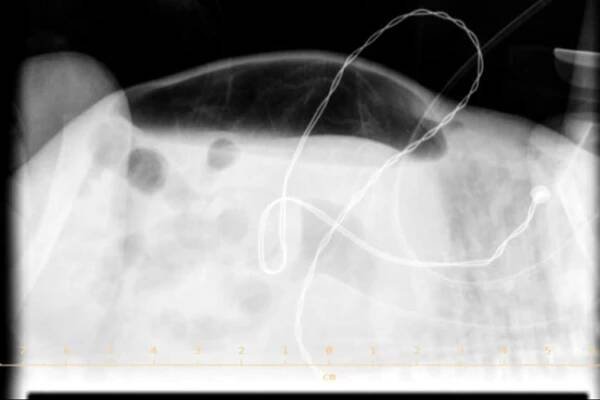

Double wall sign. This is a secondary sign of pneumoperitoneum. Patient is supine, and air within the abdomen and lumen of the bowel accentuate both sides of the bowel wall.

Česká Neonatologická Společnost • RTG abdomen 07 pneumoperitoneum

Spontaneous Intestinal Perforation | Applied Radiology